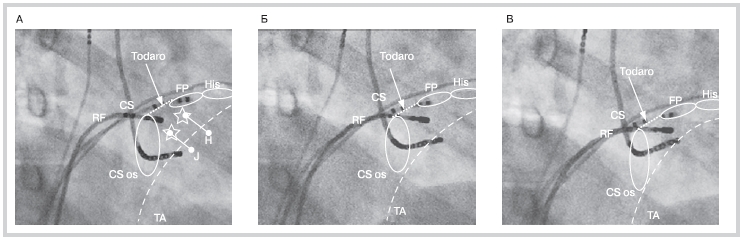

Рис. 3. Положение внутрисердечных электродов в ходе картирования нового и традиционных потенциалов «медленной» части АВС на рентгеновских стоп кадрах в правой косой проекции 40° с увеличением.

А — регистрация нового потенциала осуществлялась в наибольшем удалении от компактной части АВС (His) в области передневерхнего края коронарного синуса (CS os). Звездочками на рисунке обозначены участки картирования традиционных потенциалов W. Jackman (J) и M. Haissaguerre (H); Б, В — положение деструктирующего электрода у этого же пациента в участках регистрации потенциалов «медленной» части АВС, описанных группами W. Jackman и M. Haissaguerre соответственно. Новый потенциал регистрируется на самом значительном отдалении от компактной части АВС по сравнению с классическими потенциалами. Эндограммы с электродов представлены на рис. 2. АВС — атриовентрикулярное соединение; CS — диагностический электрод, позиционированный в коронарном синусе; RF — деструктирующий электрод; ТА — проекция кольца трикуспидального клапана; His — пучок Гиса; Тоdaro — связка Тодаро; FP— «быстрая» часть АВС.